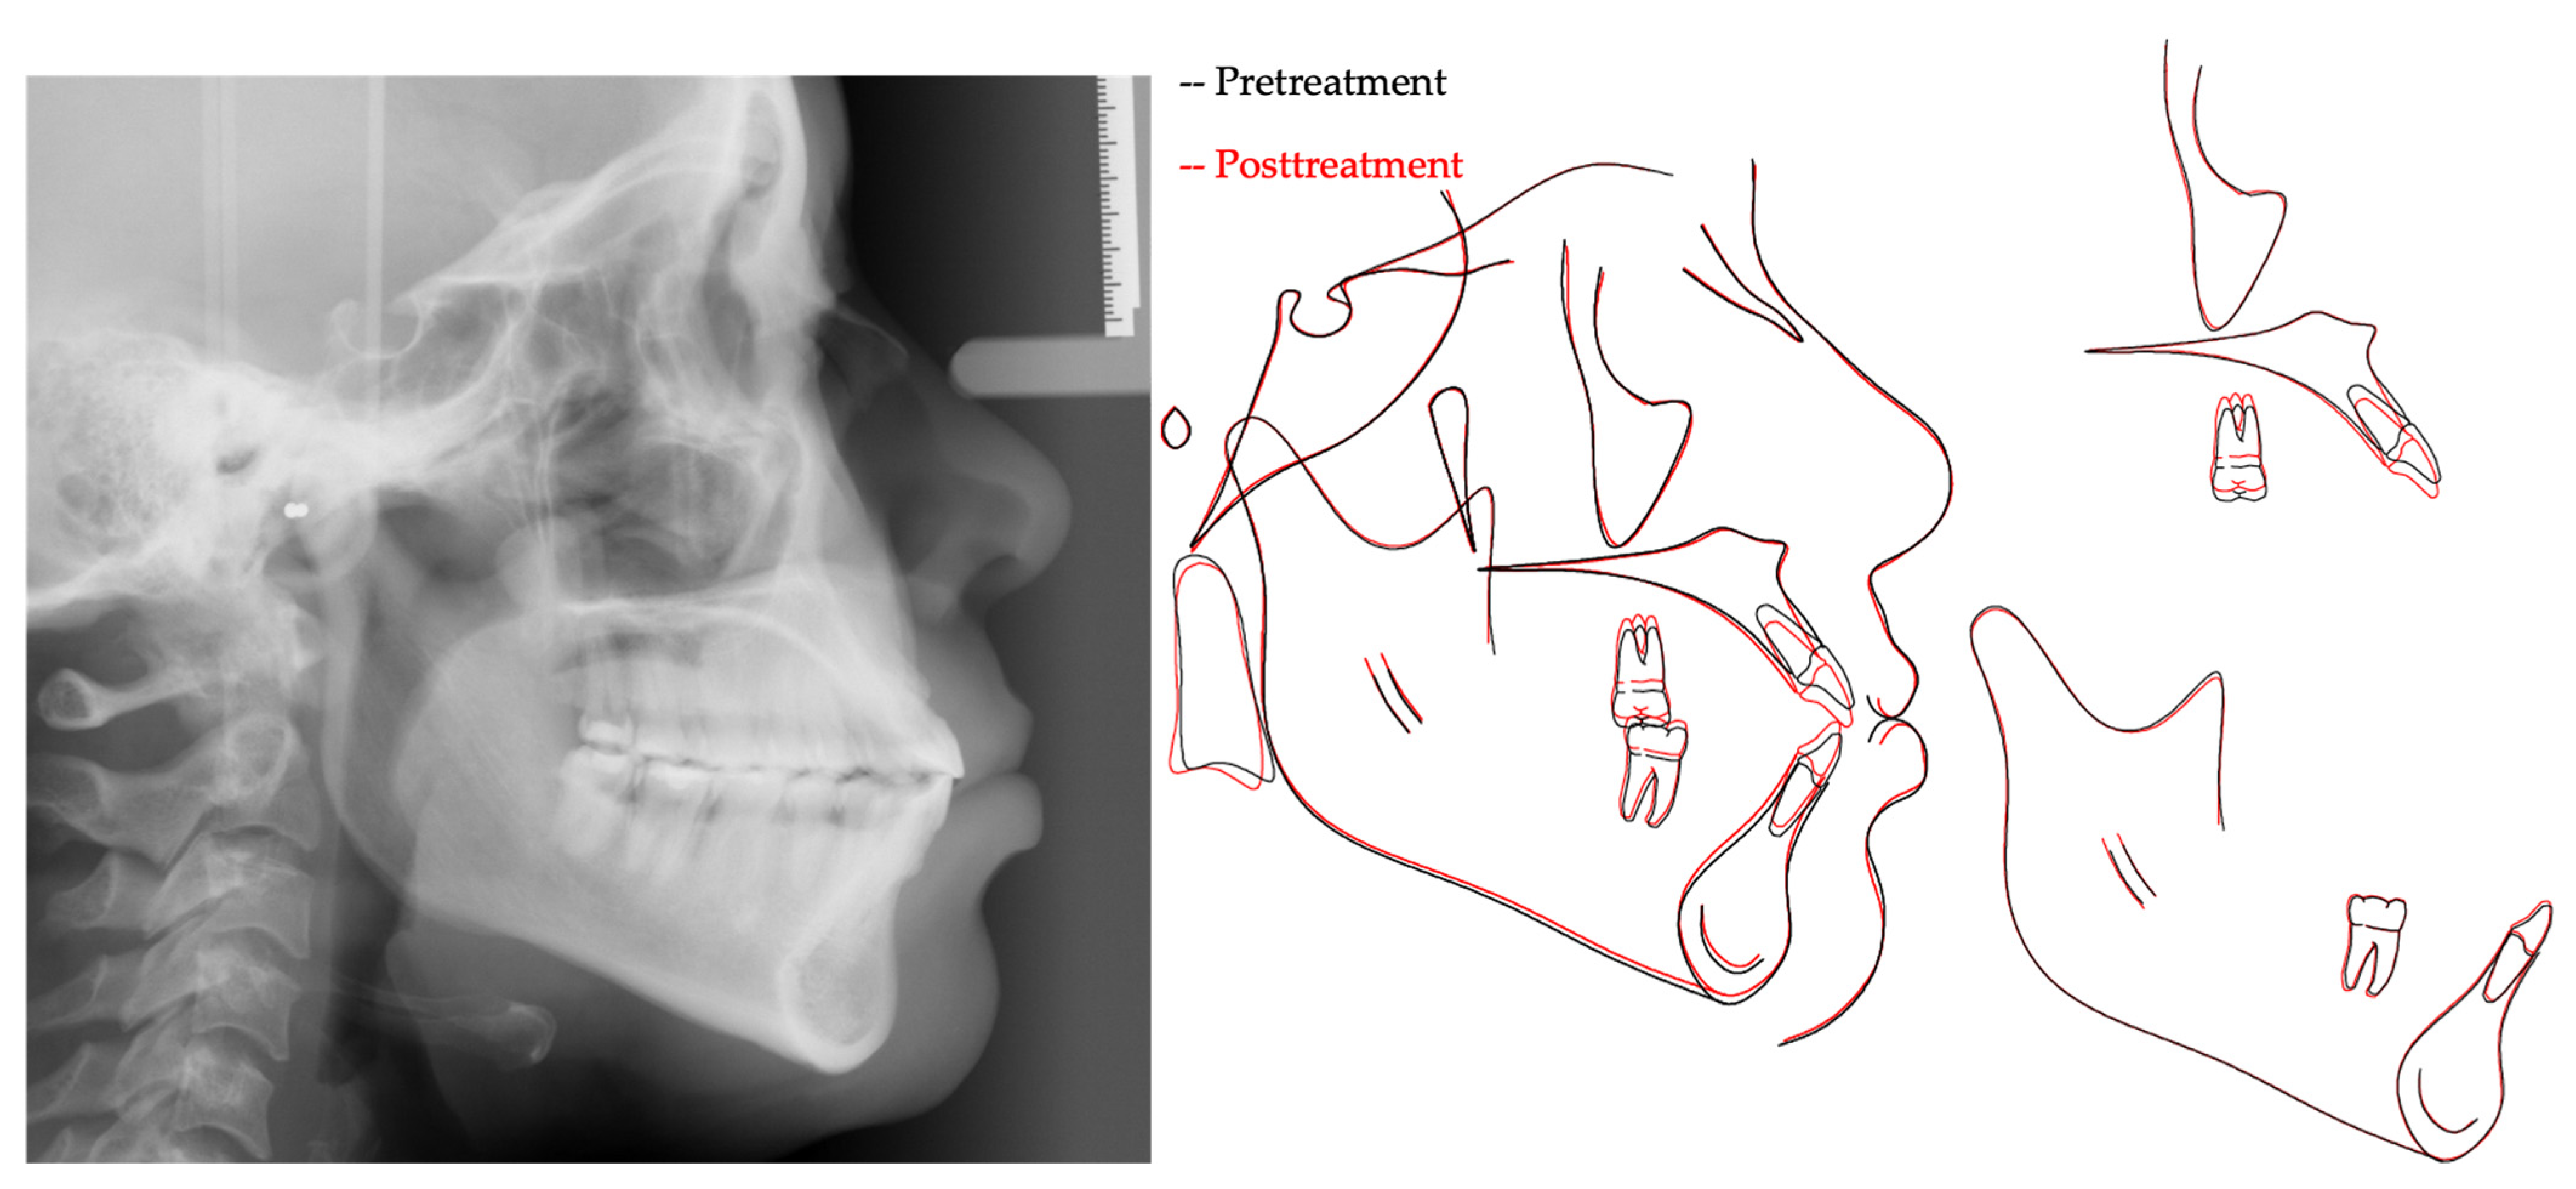

The patient’s chief complaint was addressed, and the patient-centered treatment objectives were achieved, with good esthetic and occlusal outcomes. The post-treatment result shows improvement in lip closure, smile esthetics and overbite (Figure 5). The tongue thrust habit was addressed, and the patient has become genuinely aware of its importance from a stability perspective. Along with the tipping of the occlusal planes, a normal overbite was achieved through a combination of maxillary posterior teeth intrusion, maxillary and mandibular incisors’ relative extrusion, i.e., retroclination and retraction, and mandibular autorotation (Figure 6 and Table 1). Such outcomes were accomplished via the application of miniscrew-assisted sectional mechanics, IPR and inter-arch elastics. The post-treatment panoramic and periapical radiographs showed good root parallelism, without significant root shortening, worsening of the root/crown ratio at the maxillary incisors or development of other pathologies (Figure 7). Follow-up records after 56 months demonstrated a stable occlusion with increased incisal display and an overbite (Figure 8 and Figure 9).

Figure 6.

Post-treatment cephalometric radiograph and pretreatment-to-post-treatment cephalometric superimposition (Black, pretreatment; Red, posttreatment).

It is important to consider the 3-D changes associated with intrusion of the maxillary posterior teeth. In the vertical dimension, a combination of intrusion of the maxillary posterior teeth and relative extrusion of the maxillary anterior teeth provided correction of the patient’s AOB with an improved incisal display and smile arc (Figure 5). Although she could have benefited from more incisor extrusion, such “true” extrusion would have deteriorated her periodontal status. Furthermore, it might have worsened her smile esthetics given the presence of notable black triangles (Figure 8). According to Scheffler and colleagues (2014), 2.3 mm of maxillary molar intrusion improves an overbite by 2.2 mm as opposed to the conventionally assumed 4 mm, possibly because of mandibular molar extrusion [14]. In the present case, mandibular molars were maintained, maxillary molars were intruded ~2 mm, maxillary incisors were “relatively” extruded ~3 mm, and mandibular incisors were slightly extruded. The overall change in overbite was about 5.1 mm, from an initial open bite of −3.9 mm to a final overbite of 1.2 mm.

In the anteroposterior dimension, TAD-based maxillary posterior intrusion produces counterclockwise mandibular autorotation that increases the chin projection and improves the facial profile in class II patients [9,14,15]. In our case, the mandibular plane angle became slightly decreased with the mandibular autorotation, which contributed to a more relaxed lower lip closure. We also maintained the vertical position of the mandibular posterior teeth, performed IPR at the mandibular teeth and used CL III elastics from the mandibular teeth to the maxillary TADs. As a result, the mandibular incisors were retracted and retroclined. Such changes in the anteroposterior dimension subsequently impacted the vertical dimension positively, as evident by the rotation of the occlusal planes and OB improvement. In the transverse dimension, buccal crown tipping of the posterior teeth is an adverse side effect that needs to be counteracted using, for example, a TPA or palatal TADs [9,15]. In our case, and despite using stiff rectangular sectional archwires relative to the bracket slot, we encountered such a side effect due to the use of a commercially available removable TPA that lacked proper stiffness. Buccal crown tipping of the posterior teeth in our case was later managed with cross elastics on lighter sectional upper archwires against a larger and stiffer continuous lower archwire.